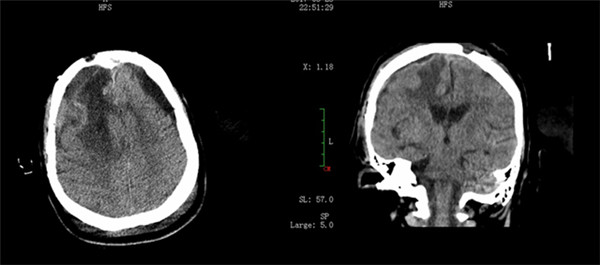

术后影像

手术结束后,得知肿瘤被全部切除,手术顺利,大家都为之捏把汗,在外等候多时的全家老小喜极而泣。经过外六科ICU术后2个小时的复苏,患者很快清醒,血压恢复正常,拔出气管插管;术后第二天,患者语言正常,右眼视力逐渐恢复,癫痫症状消失,四肢逐渐恢复活动。经过术后康复治疗及护理,相信患者一定能早日康复出院。